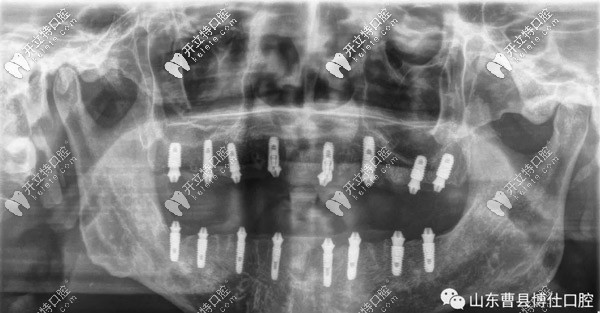

經(jīng)過一個半小時的手術(shù)時間,徐大爺上頜和下頜各植入8顆種植體,縫合傷口后,拍片顯示植入位置非常好。

之后,于院長帶領(lǐng)博仕口腔的即刻修復(fù)團(tuán)隊(duì)開始排牙、注膠、打磨、調(diào)咬合、拋光等,下午6點(diǎn)左右為徐大爺帶上了新牙。

通過拍片顯示,臨時牙和螺栓結(jié)合非常緊密,不需要調(diào)整,也經(jīng)過多次的反復(fù)咬合之后,并沒有不適的情況。